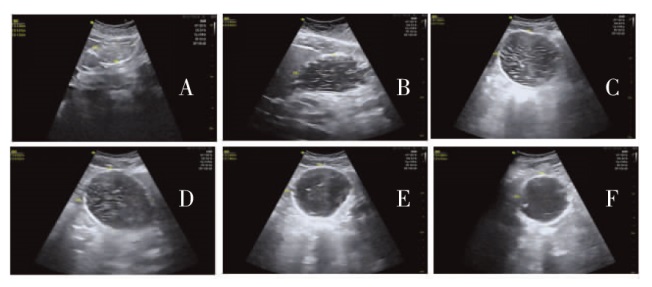

| [7] | Shin HJ, Koo BW, Lim D, et al. Ultrasound assessment of gastric volume in older adults after drinking carbohydrate-containing fluids:a prospective,nonrandomized,and noninferiority comparative study[J]. Can J Anaesth, 2022, 69(9):1160-1166. |

| [19] | 孙建华, 张青, 李欣, 等. 重症超声临床操作技术的护理规范[J]. 中华现代护理杂志, 2023, 29(16):2101-2112. |

| Sun JH, Zhang Q, Li X, et al. Nursing standards of clinical practice of critical care ultrasonography[J]. Chin J Mod Nurs, 2023, 29(16):2101-2112. | |

Haramgatti A, Sharma S, Kumar A, et al. Comparison of ultrasound-guided residual gastric volume measurement between diabetic and non-diabetic patients scheduled for elective surgery under general anesthesia[J]. Saudi J Anaesth, 2022, 16(3):355-360.

DOI PMID |